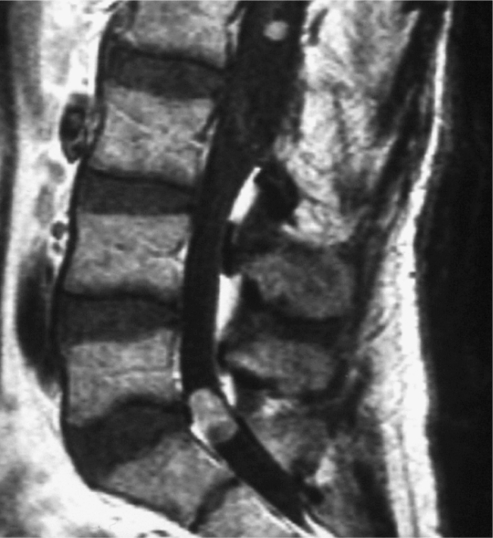

Fig. 3.

Lumbar Intradural lesion (case 2)